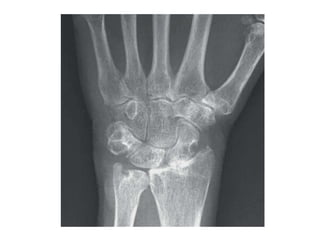

評估疾病的新工具 • X光 • 超音波 •

核磁共振